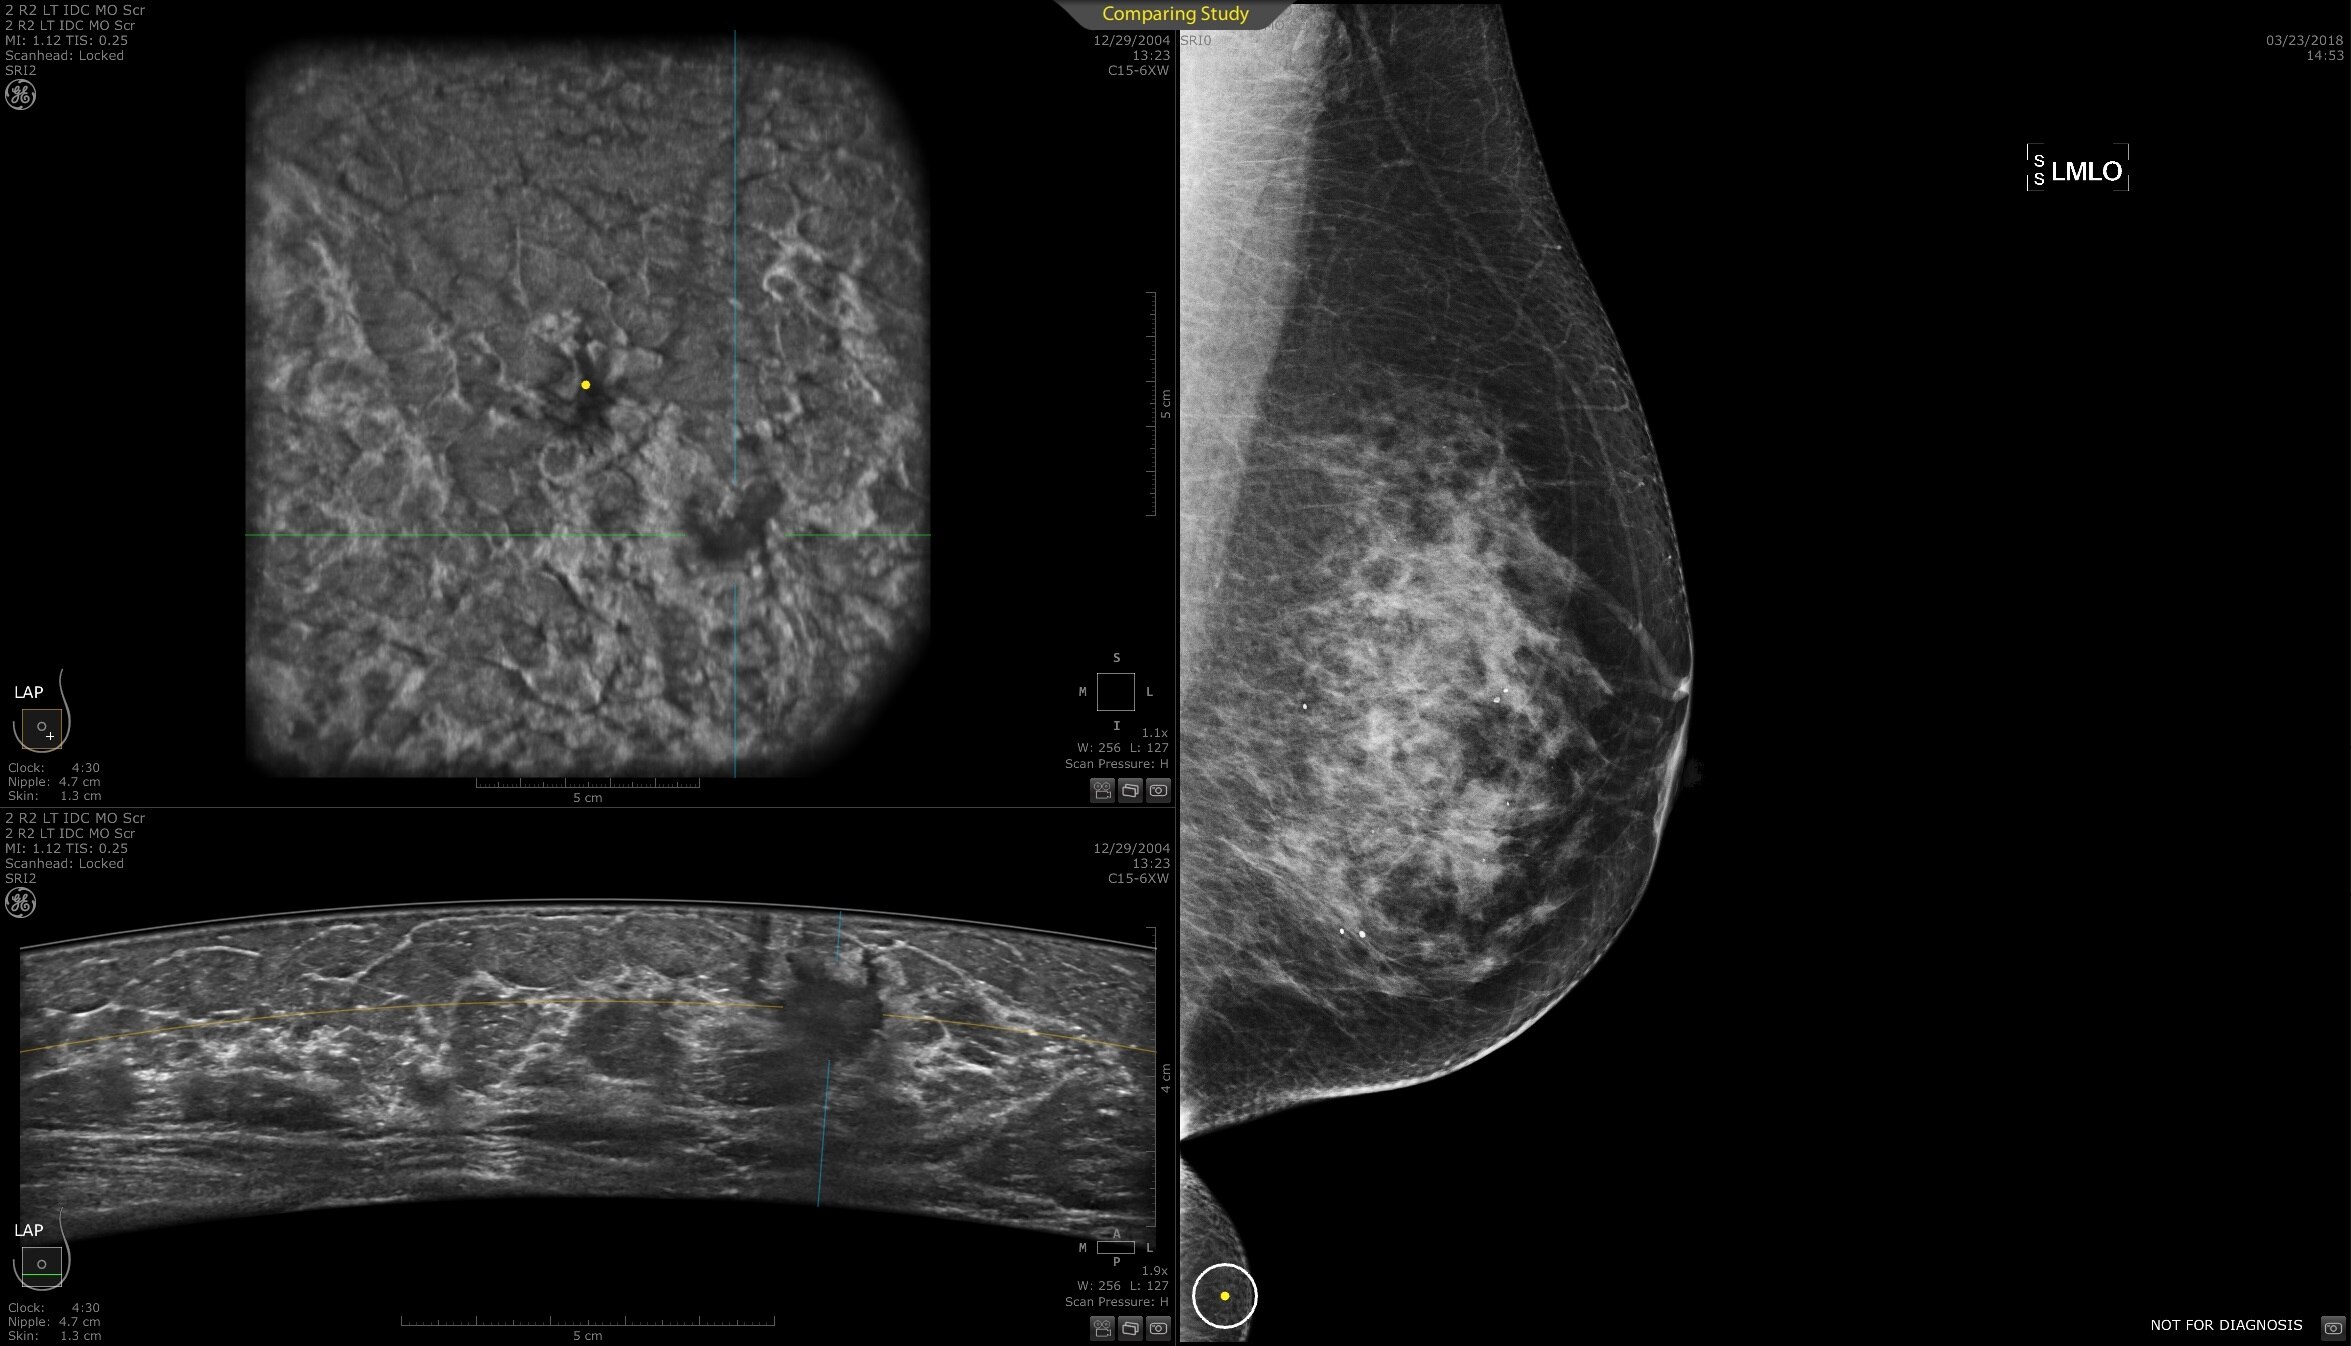

DIAGNOSIS & STAGING

Lesion characterization for confident staging in dense breasts

Invenia ABUS 2.0 uses the latest ultrasound innovations and AI based solutions to help improve precise diagnosis and elevate clinical confidence.